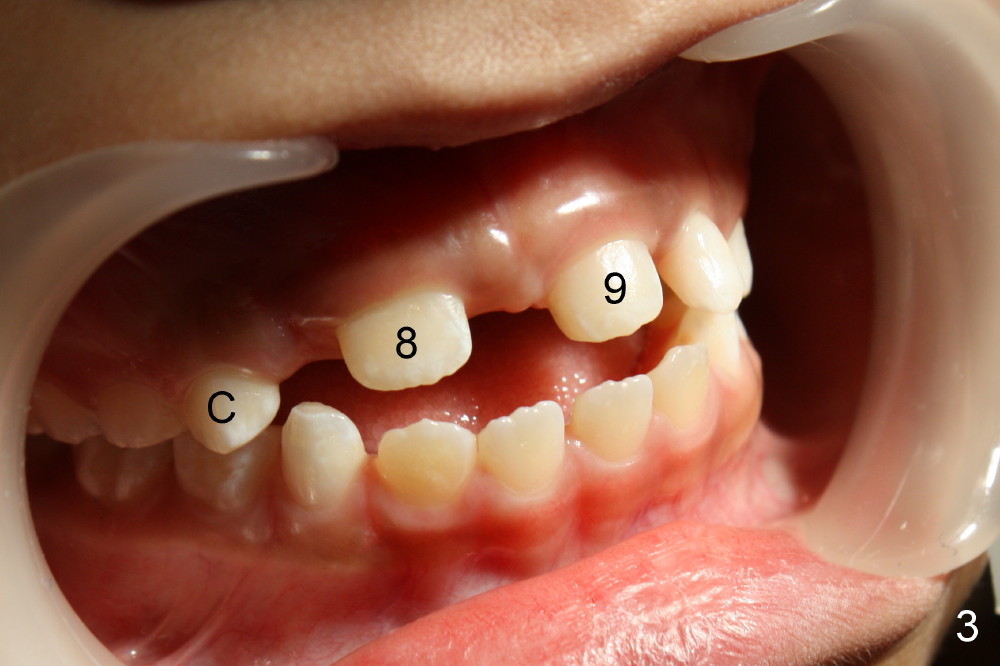

A seven-year-old co-operative boy presented to my office for composite. Exam shows open bite and a large diastema between the erupting upper central incisors (Fig.1-4). His mother notices that the diastema is more due to lateral displacement of the right central than the left central's (compare to Fig.1: black dashed line). She asks whether the uneven displacement will interfere with eruption of the upper right lateral incisor (Fig.2,3, as compared to Fig.4). She is interested in early ortho.

There are three questions. Will the right lateral erupt by itself and the diastema self corrects? When can we start ortho? How can we treat deep cingulum of #9 (Fig.2 >), removing marginal ridges or placing composite in the cingulum? The purpose of cingulum treatment is to prevent caries. Do we also need to add composite to #9 proximal surfaces to make it look as wide as #8? Thanks.